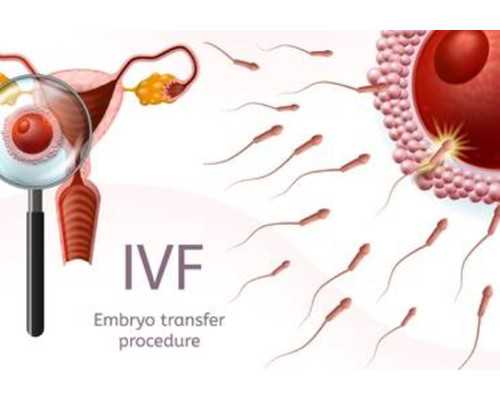

捐卵試管技術(shù):一代捐卵、二代捐卵

考慮到代孕協(xié)議的非法性和風(fēng)險(xiǎn),建議代孕人和受孕方尋求其他替代方案,如領(lǐng)養(yǎng)、試管嬰兒等。這些方案都是合法的,可以有效地解決生育難題。同時(shí),政府和社會(huì)也應(yīng)該加強(qiáng)對(duì)代孕行業(yè)的監(jiān)管和管理,保護(hù)代孕人和受孕方的合法權(quán)益。